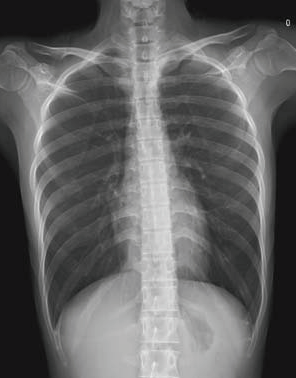

Although digital X-ray machines are simple to operate and can generate an image within 10 seconds, they can only provide a single flat image, which limits their diagnostic ability in complex trauma cases.

When performing CT scan examination for a patient injured in a car accident, doctors can obtain images of full body in five to ten minutes. These images can help them immediately identify life-threatening injuries such as cerebral hemorrhage, pulmonary contusions, and lacerations of the internal organ, which is vital for doctors to implement target treatment (e.g., blood pressure control, respiratory function maintenance, emergency hemostasis).